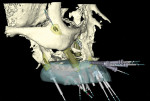

The finalized virtual implant plan (Figure 8 through Figure 12) consisted of two 10-mm implants and one 13-mm implant in the maxillary anterior region, which engaged the cortical bone at the inferior border of the nasal cavity. The plan called for two 18-mm implants to be placed in the pterygomaxillary31,32 region at an approximately 45-degree angle to the occlusal plane. These pterygomaxillary implants would provide posterior support for the restoration and eliminate a posterior cantilever.33-36 In order to shorten the span between the three anterior and two posterior implants, three zygoma implants were planned on the pre-surgica lcomputer model to transect through the sinus cavity and engage the zygoma bone. All implants in the virtual planning were external-connection regular-platform implants (Brånemark® System, Nobel Biocare).

Once the zygoma implants were positioned virtually, the sizes of each zygoma implant were recorded and screenshots of the planning were taken. The virtual zygoma implants were then switched to standard-length implants in the exact same axis (Figure 13). The appropriate surgical template sleeve accompanied the standard-length implants, which could be incorporated into the surgical template. While these standard Brånemark sleeves would not permit actual zygomatic implant placement, they would enable the surgeon to create a starting point for the access of the zygoma position into the alveolar bone. This provided the ability to put the coronal aspect of the zygoma implant in the best prosthetic position, which is a tremendous advantage for laboratory construction of the final prosthesis. It also gives the surgeon an opportunity to study the 3-D anatomy of the patient prior to the surgery.

The standard-length implants were installed following the normal guided-surgery protocol.23-30 The pterygomaxillary implant on the patient’s left side had much higher primary stability than anticipated from the virtual planning; therefore, only one of the two zygoma implants was installed on that side. Then, using a 3-mm twist drill through the surgical template (Figure 14), the zygomatic implant entry through the alveolus into the sinus was made. The surgical template was then removed. A crestal-palatal incision was then made connecting the implants in the pterygomaxillary region and establishing the access points for the zygoma implants. A vertical releasing incision was made in the canine region. With the full flap reflected, Caldwell-Luc type sinus entry was made to then completely visualize the path of drilling for the zygoma implant. The implant was then placed freehand through the entry position marked by the template through the sinus and through the lateral wall of the zygoma bone. While the zygoma implant length used surgically via this partially guided approach may not be exactly the same length as the zygoma implant virtually planned, the advantage of knowing the ideal coronal position reduced the complexity of the implant placement and optimized the prosthetic orientation of the implant.